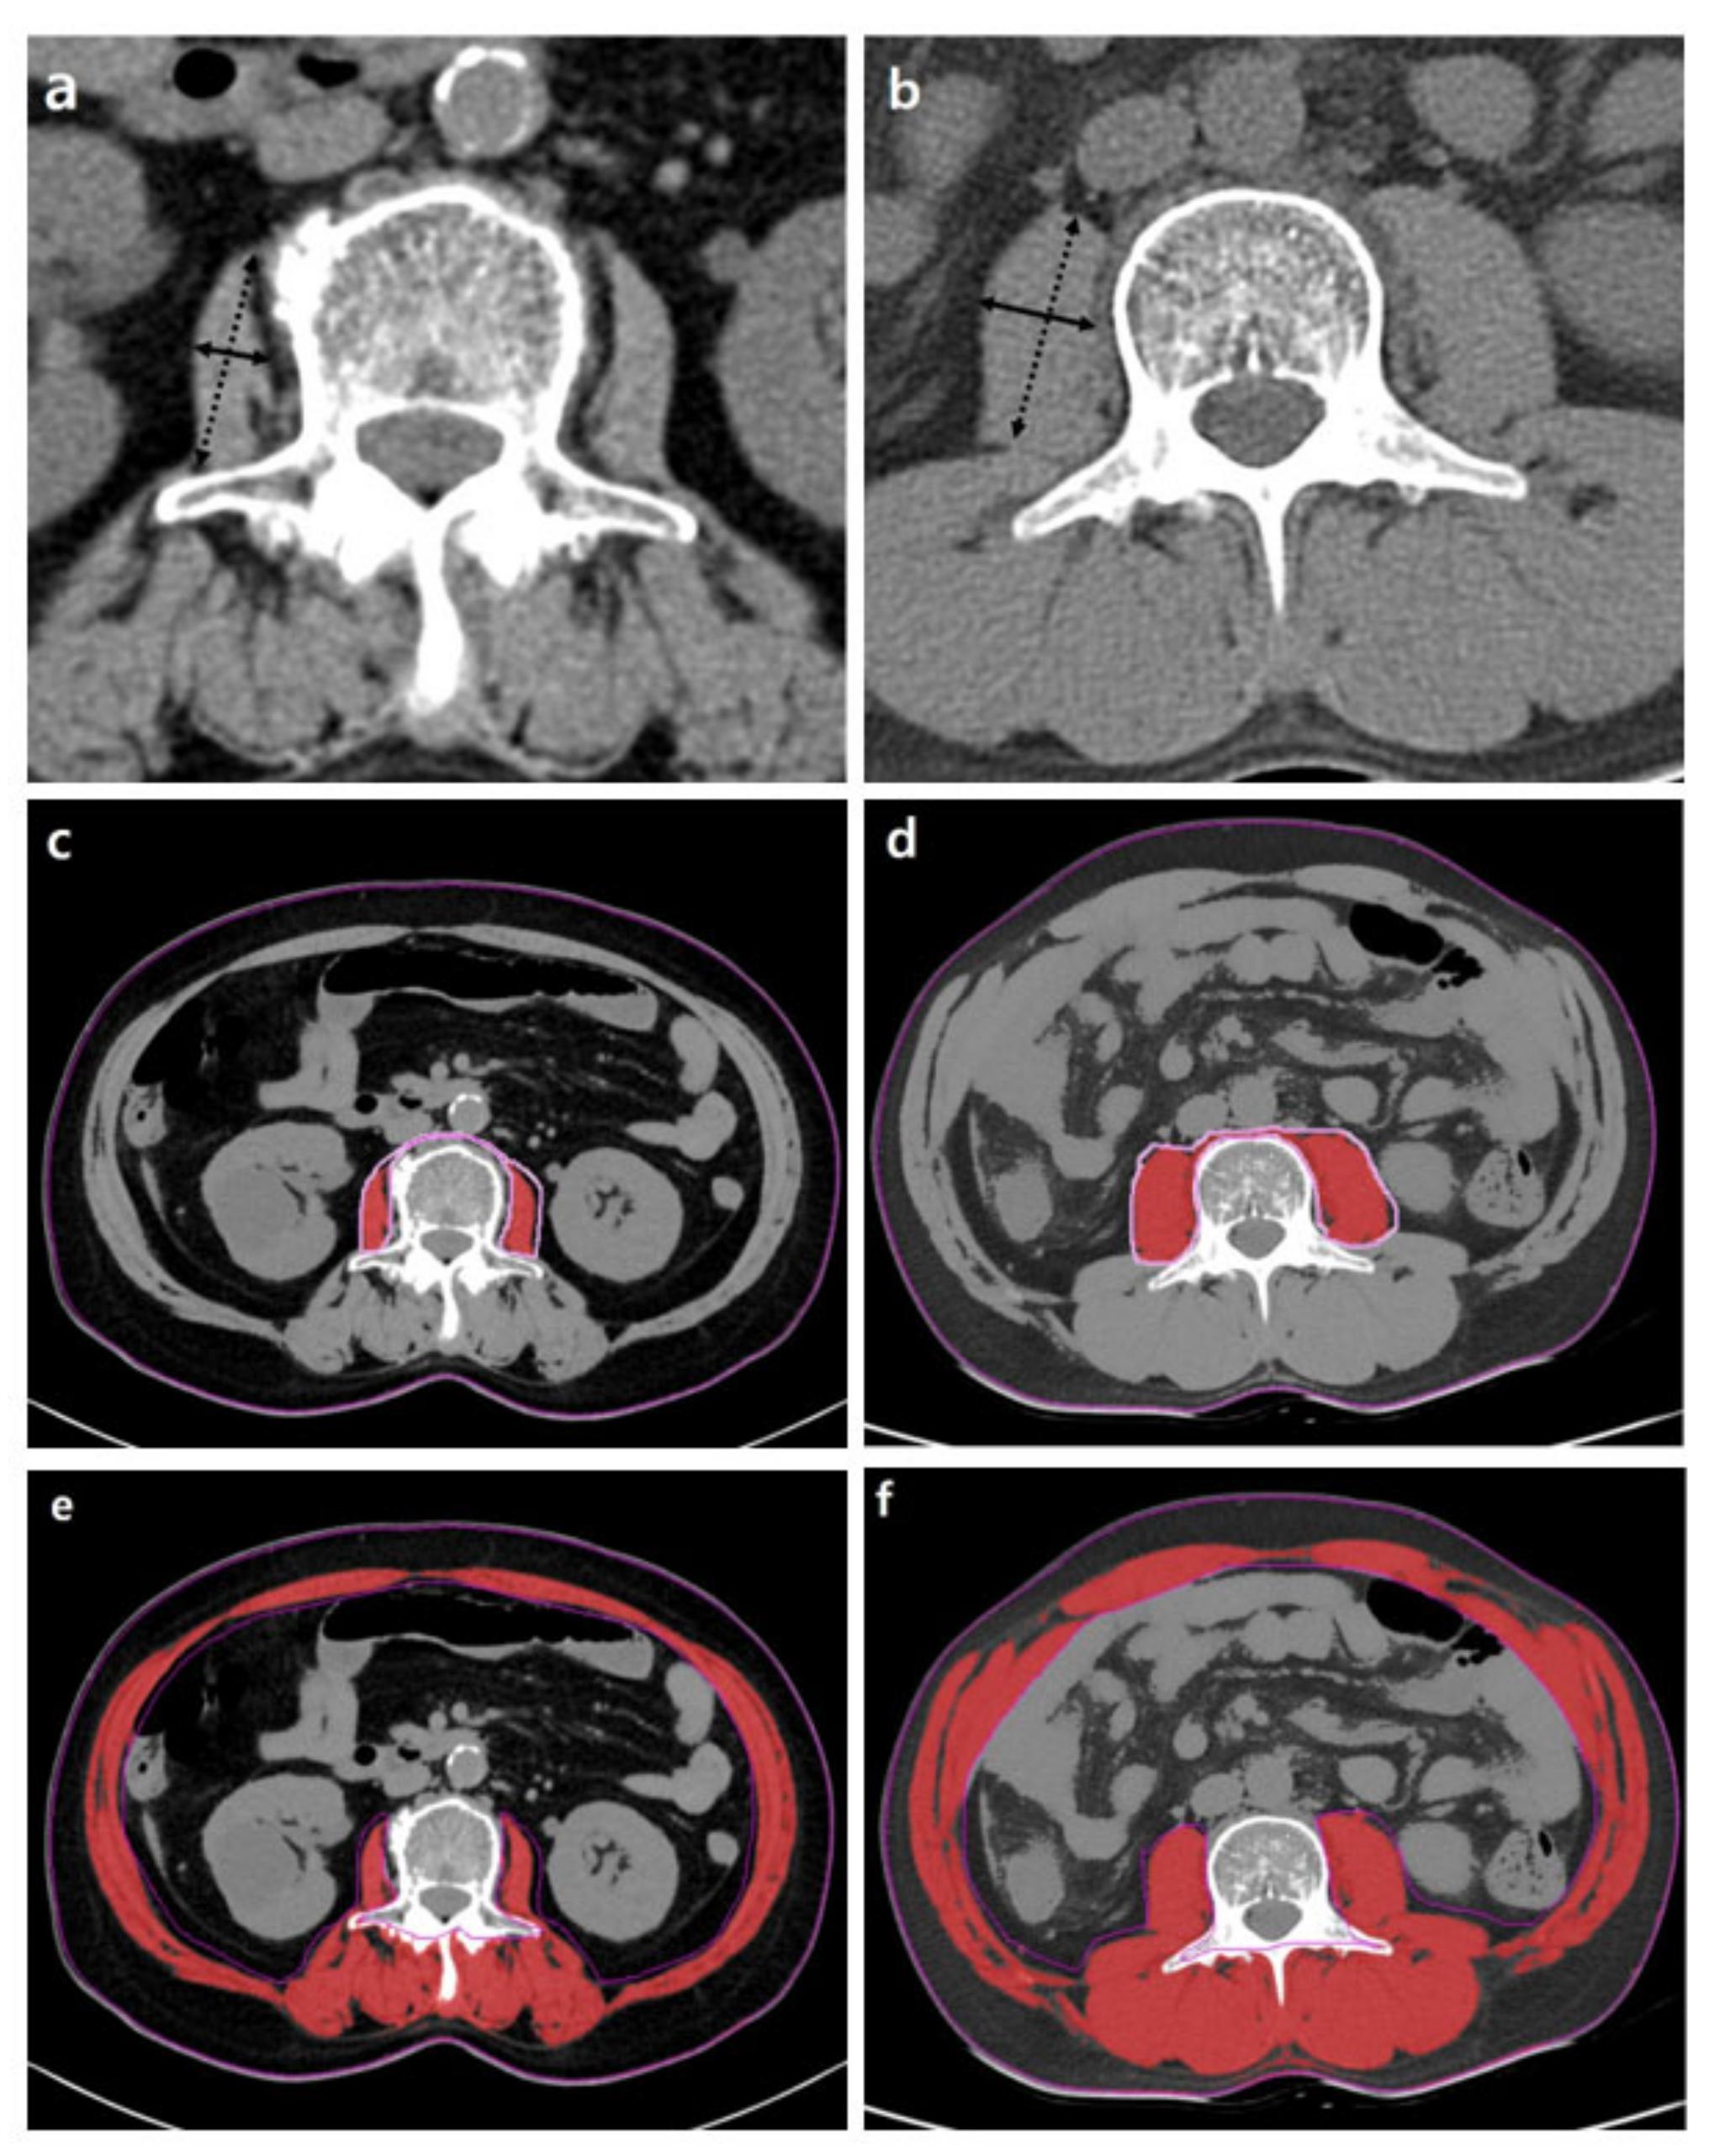

Generally, the cross-sectional areas of the psoas or abdominal muscle mass of the third (L3) or fourth (L4) lumbar vertebra levels that are not affected by activity are used. Although the cross-sectional area of the level of the umbilicus has previously been used [26], this area may be measured at different levels of the vertebra. Moreover, the umbilicus may become flat and unable to be found on axial CTs in patients with ascites or obesity [43]. Measuring should be conducted at the cross-sectional area of the skeletal muscles at the level of L3, which accurately represents the whole-body skeletal muscle mass [44]. At the L3 transverse section, muscle groups include the rectus abdominis, transverse abdominis, internal and external obliques, quadratus lumborum, psoas major and minor, and erector spinae. These measurements were computed by summing the tissue pixels and multiplying them by the pixel surface area. A threshold range of 29 to 150 HU is commonly used to define the muscle (Figure 3).

Figure 3.

Abdominal CT images taken at the third lumbar vertebra with cirrhosis applied to quantify transverse psoas muscle thickness (TPMT), psoas muscle, and total muscle areas. The psoas muscle in panels (c,d) and total muscle area in panels (e,f) are colored in red. Panels (a,c,e) present a female patient with low TPMT (5.9 mm/m), psoas muscle index (PMI) (2.3 cm2/m2), and skeletal muscle index (SMI) (35.7 cm2/m2). Panels (b,d,f) present a male patient with high TPMT (23.3 mm/m), PMI (6.8 cm2/m2), and SMI (51.6 cm2/m2). The mean density of muscle in (c–f) is 34.7, 38.2, 26.2, and 36.6 HU, respectively.